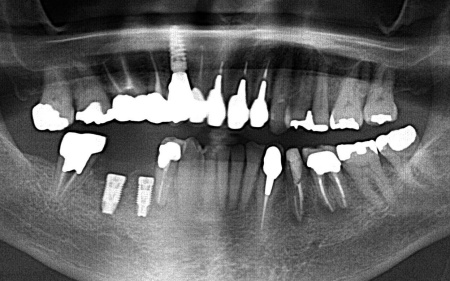

歯やあごの骨の状態を詳しく調べるためレントゲン検査を行った結果、右下の奥歯2本(第2小臼歯、第1大臼歯)は、歯根が縦方向に割れている可能性が高いと考えられました。 しかし、レントゲン画像だけでは歯根の状態を正確に判断することはできません。 歯根が割れている場合、細菌感染が進行して歯ぐきの炎症が広がったり周囲の歯やあごの骨にまで影響を及ぼしたりする可能性があります。 以上のことから、歯を温存することは難しいため抜歯が必要と診断しました。 |

| 行ったご提案・治療内容 | 診断結果を丁寧に説明したうえで、右下奥歯2本の抜歯を提案したところ同意いただきました。 併せて抜歯後に歯を補う方法として、以下2つの選択肢をお伝えしました。 ①前後の歯を削って橋のようにつなげた被せ物で歯を補うブリッジ治療 ②あごの骨に人工の歯根を埋め込み、その上に人工歯を取り付けるインプラント治療 それぞれの特徴や注意点について説明したところ、患者様は②のインプラント治療を希望されました。 まず右下奥歯2本の抜歯を行い、その後、約3ヶ月間歯ぐきや骨が十分に回復するのを待ちました。 |